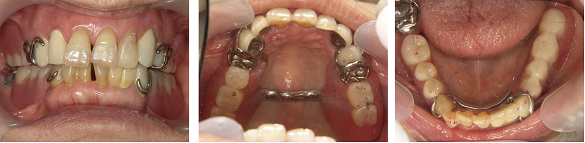

最終的な被せ物を入れた状態です。

伸びてしまっていた歯の位置関係を改善することで、スムーズな咀嚼を可能とし、また、ブリッジ部分をインプラントに変えたことで長期的にも安定したかみ合わせを作ることが出来ました。

また、かぶせ物に白い材料を選ぶことで、審美的にも良好な結果を得ることが出来ました。